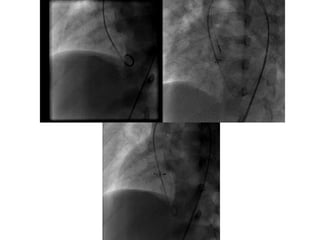

Device selection

 Type of the device

 Size of the device

Determinants of the Device type

 Size of the defect

 Morphology of the defect

Size of the defect

 ADO II : upto 5.5 mm

 Nit Occlud Le VSD coil : upto 8 mm

 ADO I : upto 12 mm

 AAPMVSDO & AMVSD occluder : upto 16 mm

 Modified Membranous VSD occluders

(Lifetech and Shanghai Steel Corp) : upto 19

mm

Sizing the device

 No definite guidelines

 Echo Vs Angio

 LV Vs RV

 APMVSDO: RV side of the defect. Measure in

two planes. Average and add 1

 ADO I: RV side of the defect + 1 or 2 =

Pulmonary end of the ADO I

 ADO II: RV side of the defect + 0.5 to 1 mm